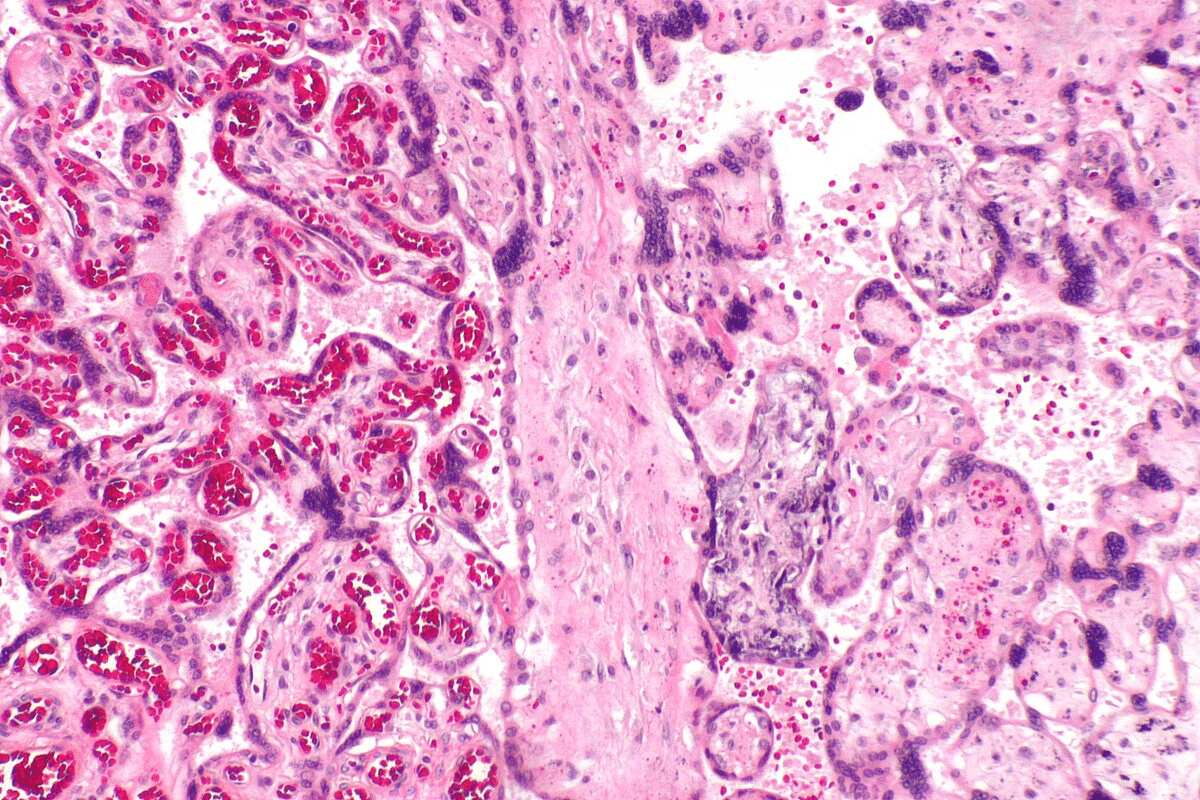

Diagnosing and Differentiating Cutaneous Lupus

To diagnose cutaneous lupus erythematosus (CLE), we use a detailed approach. This includes looking at the skin, taking biopsies, and running lab tests. Getting the diagnosis right is key to treating the condition well.

Clinical Examination Techniques

First, we do a thorough check of the skin. We look at the skin lesions, their shape, and where they are on the body. For example, a rash on the chest or back might point to CLE.

Key aspects of clinical examination include:

- Visual inspection of skin lesions

- Assessment of lesion distribution and morphology

- Evaluation of associated symptoms such as pain or itching

Skin Biopsies and Laboratory Tests

Biopsies are vital to confirm CLE. They help us see changes in the skin that are typical of CLE. Lab tests, like checking for ANA, also help confirm the diagnosis.

Laboratory tests may include:

- Complete Blood Count (CBC)

- Erythrocyte Sedimentation Rate (ESR)

- Serological tests for autoantibodies

Distinguishing Lupus Rashes from Other Skin Conditions

It’s important to tell CLE apart from other skin issues. We look at the patient’s history, the rash, and lab results to make a correct diagnosis. Other conditions like autoimmune diseases, infections, and drug reactions can look similar to CLE.

Key factors in differentiation include:

- Clinical presentation and rash characteristics

- Patient history and associated symptoms

- Laboratory test results

By using a mix of skin checks, biopsies, and lab tests, we can accurately diagnose CLE. This helps us give the right treatment to our patients.